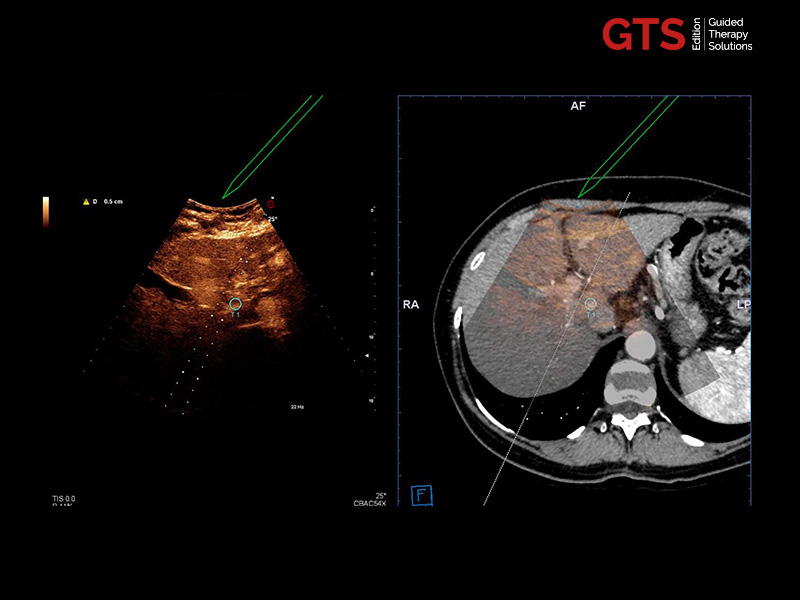

CnTI™ is Esaote’s CEUS technology that helps to identify suspicious areas in the prostate, helping to target areas to be biopsied. Furthermore, it can be used for focal therapy follow-up.

The CnTI™ guarantees a very high sensitivity in detecting contrast media agents, while maintaining long persistence of the contrast bubbles.

CnTi™ (Prostate perfusion study - Suspected anterior lesion)